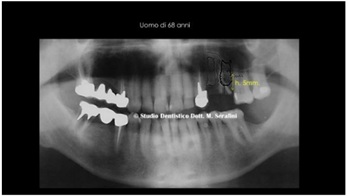

68-year-old male, one post-extraction implant and another not post extractive, with residual bone height of mm.

5 from the antral cavity, it is necessary to extract the 1.5 for coronal and radicular fracture (Figures 13,14).

Figure13: Initial Orthopantomography.

Figure 14: Clinical Case with extraction of the fractured root.

The planning fore was the insertion of two implants, 1.4 and 1.5 post-extraction with 2s Crestal Sinus Lift.

After the avulsion and careful dressing (toilette) of the surgical site, 2 implants were inserted, a standard 3.75 di 13mm and a 2s implant for the crestal Sinus Lift (Yellow arrow in figure 15).